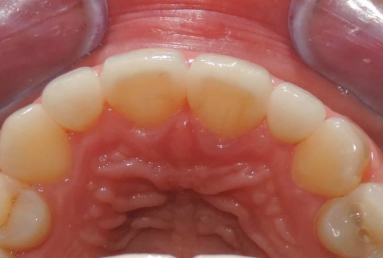

Very small lateral incisors covered with full ceramic crowns and ceramic veneers on central incisors. The prosthetic space was correctly split between the four incisors, in order to reduce the disproportion between the large centrals and the very small laterals. The preparation of the teeth was minimally invasive, all four incisors remained vital.